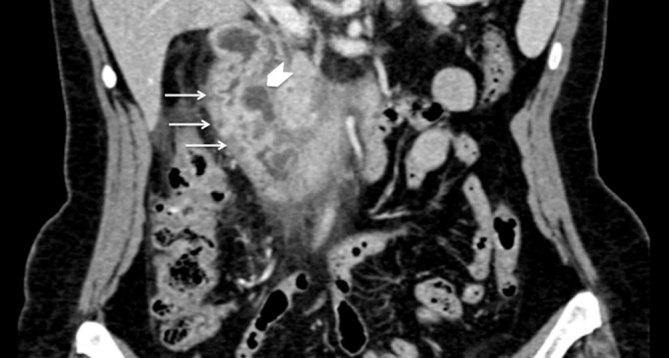

Cystic dystrophy of the duodenal wall in heterotopic pancreas, recently described as paraduodenal pancreatitis, is a rare condition characterized by multiple cysts or pseudocysts located in the submucosa or muscularis propria of a thickened duodenal wall. They result from multiple episodes of obstruction of the small ducts in aberrant pancreatic islets. Cystic dystrophy of the duodenal wall in heterotopic pancreas usually affects alcoholic males, but here we present the case of a female without a history of alcohol abuse who was referred to our emergency department with abdominal pain and vomiting. She was treated by a pancreas-preserving surgical approach, thanks to a proper pre-operative differential diagnosis. Even though differentiating this benign condition from pancreatic cancer is a challenge, some characteristic findings on multidetector CT scan and MRI/MR cholangiopancreatography, such as a thickened duodenal wall containing cysts and sheet-like tissues in the pancreaticoduodenal groove, could lead to the correct diagnosis.

十二指肠壁囊肿性营养不良合并异位胰腺,最近被描述为十二指肠旁胰腺炎,是一种罕见的病症,其特征是在增厚的十二指肠壁的黏膜下层或固有肌层中存在多个囊肿或假性囊肿。它们是由异常胰岛中小导管的多次梗阻引起的。十二指肠壁囊肿性营养不良合并异位胰腺通常影响男性酗酒者,但在此我们报告一例无酗酒史的女性病例,该女性因腹痛和呕吐被转诊至我们的急诊科。由于术前进行了恰当的鉴别诊断,她接受了保留胰腺的手术治疗。尽管将这种良性病症与胰腺癌区分开来具有挑战性,但多排CT扫描和MRI/MR胰胆管造影的一些特征性表现,如十二指肠壁增厚并伴有囊肿以及胰十二指肠沟内的片状组织,可有助于做出正确诊断。